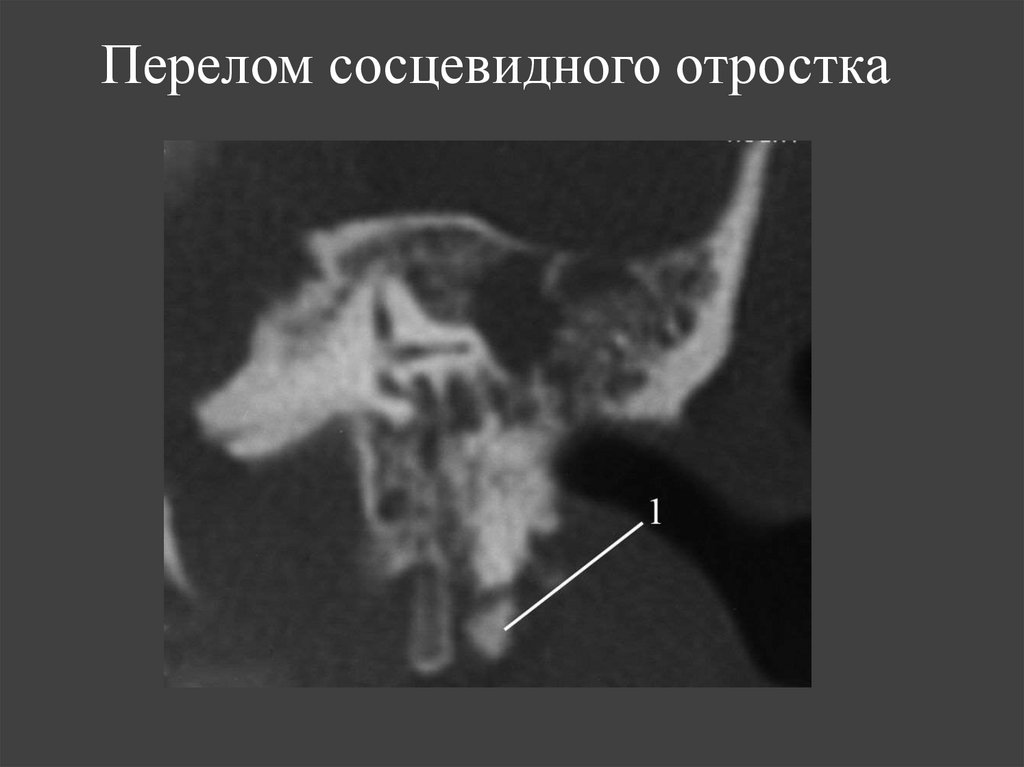

12. Перелом сосцевидного отростка